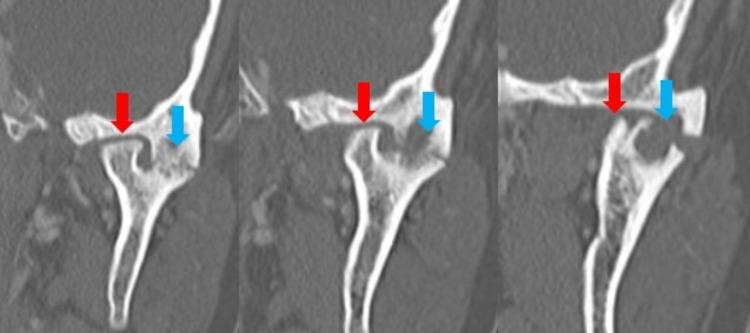

Bifid mandibular condyle (BMC) is splitting the mandibular condyle into two separate articular surfaces. The etiology is poorly understood, but trauma and developmental issues are currently the most cited causes. Though most often asymptomatic, occasionally, this condition may cause the development of jaw pain, clicking, and restriction of motion. We present a rare case of a patient who developed unilateral ankylosis of the temporomandibular joint (TMJ) secondary to BMC in the absence of trauma or infection. The ankylosis developed due to abnormal biomechanical forces and degenerative arthritis secondary to the abnormal articulation of the TMJ caused due to BMC. CT imaging is the best modality to evaluate the bony anatomy of the TMJ. It is essential to consider BMC as a cause of TMJ pathology, as management is primarily surgical in nature.

双侧下颌髁突(BMC)是指下颌髁突分裂为两个独立的关节面。其病因尚不清楚,但目前最常提及的原因是创伤和发育问题。尽管大多数情况下无症状,但偶尔这种情况可能会导致颌部疼痛、弹响和运动受限。我们报告了一例罕见病例,一名患者在没有创伤或感染的情况下,继发于BMC出现了颞下颌关节(TMJ)单侧强直。强直是由于BMC导致TMJ异常关节连接所产生的异常生物力学力量和退行性关节炎引起的。CT成像 是评估TMJ骨解剖结构的最佳方式。必须将BMC视为TMJ病理的一个原因,因为治疗主要是手术性质的。